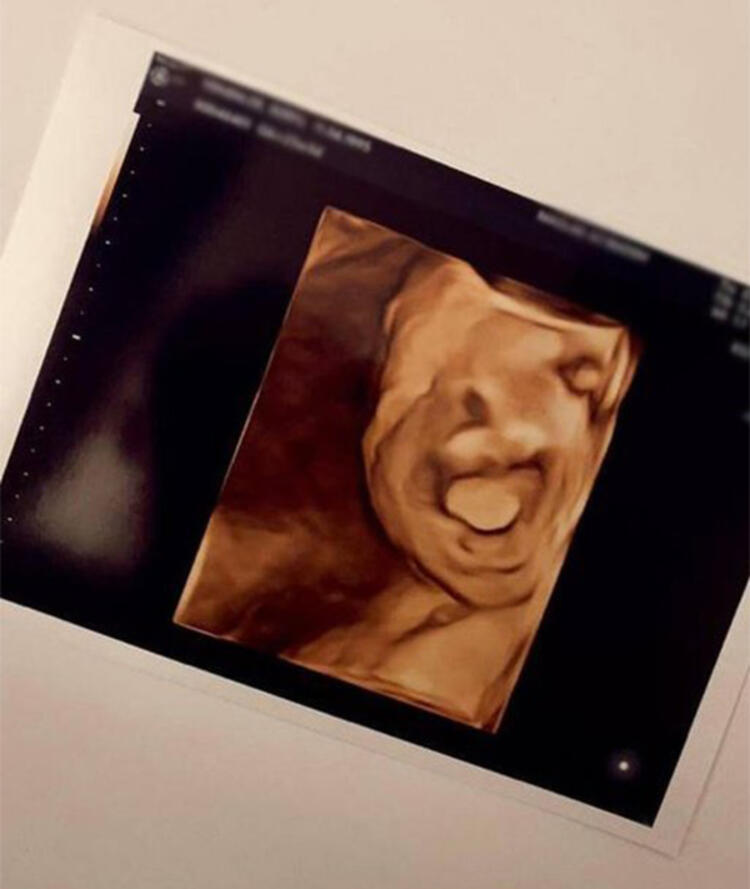

Eser Yenenler ile 2019 yılında nikah masasına oturan Berfu Yenenler, ikinci kez hamile olduğunu duyurmuştu. Geçtiğimiz günlerde ultrason görüntülerini paylaşan Berfu Yenenler'den karnı burnunda yeni pozlar geldi. Yenenler'in 'Göbüş güncellemesi' notunu düştüğü paylaşımına çok sayıda beğeni ve yorum geldi.

Ünlü oyuncu Eser Yenenler'in 2019 yılında hayatını birleştirdiği tescilli güzel Berfu Yenenler'in ikinci kez hamile olduğu haberi geçtiğimiz aylarda ortaya çıkmıştı.

İkinci çocuğunu kucağına almak için gün sayan Berfu Yenenler, belirginleşen karnı ile verdiği pozu sosyal medya hesabından yayınladı.

25 yaşındaki Berfu Yenenler, karnı burnunda pozuna, "Göbüş güncellemesi... 26+1 Mete emmisiyle karşınızdayız. Zaman ne çabuk geçiyor inanamıyorum. Sanki daha yeni Kuzey'e hamileydim ve şimdi Mete'nin doğumuna gün saymaya başlayacağım neredeyse, çok heyecanlı" notunu düştü.